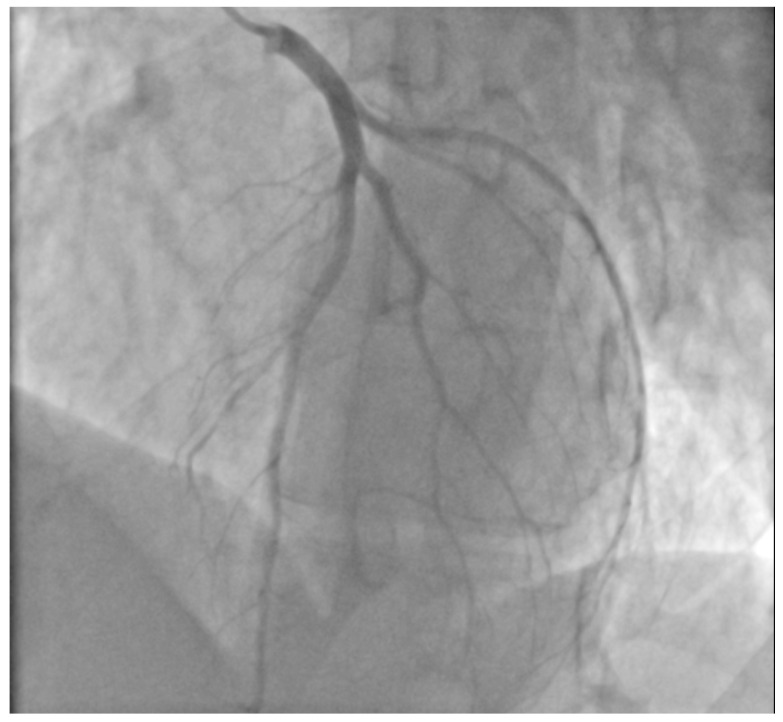

A 29-year-old male patient, a manual worker without history of overt infectious myocarditis, without classic risk factors for cardiovascular diseases, with mixed anxiety and depressive disorder, was treated with prescribed off-label medical marijuana (delta-9-tetrahydrocannabinol THC 19% and cannabidiol CBD < 1%, bred from Lemon Skunk Cannabis Strain in the form of unprocessed dried leaves) for around 3 years, smoked at least 3–4 times a day and was diagnosed with severe cannabis use disorder (continued use of cannabis despite clinically significant impairment) [ref. 6]. It was diagnosed by a psychiatrist according to the fifth version of the Diagnostic and Statistical Manual of Mental Disorders (DSM-5) with 8 out of 11 criteria met: hazardous use, social/interpersonal problems, neglected major roles, withdrawal, used larger amounts/longer, much time spent using, activities given up and craving [ref. 7]. Moreover, the patient was categorized as a chronic user [ref. 8]. He had been suffering from paroxysmal hemodynamically unstable ventricular tachycardia (VT). The first episode occurred 30 months ago and the patient was referred from an emergency room to a distant cardiology center, where upon coronarography, apart from myocardial bridge localized in the middle segment of the left anterior descending coronary artery no lesions in the coronary arteries were recorded. There were no specific abnormalities recognized in resting ECG (Figure 1, left panel). In the echocardiogram the structure and function of the heart was normal, apart from a mildly compromised left ventricular systolic function with left ventricular ejection fraction (LVEF) of 43%. At that time the patient did not consent to the proposed diagnostics of VT consisting of cardiovascular magnetic resonance imaging of the heart, electrophysiological study, genetic testing and therapy with subcutaneous implantable cardioverter-defibrillator. He received metoprolol in extended-release drug formulation (metoprolol succinate) of 25 mg q.d. due to intolerance of higher doses, potassium, magnesium and vitamin B6 supplementation. Within this period, the subject experienced at least six episodes of VT that required medical assistance. Moreover, 7 months earlier he was admitted to the catheterization unit again after an acute episode of retrosternal pain following marijuana intake. Once more, no lesions within the coronary arteries were observed in coronarography (Figure 2 and Figure 3). ECG showed no signs of ischemia, echocardiography was without segmental dysfunction of cardiac muscle, and LVEF equaled 40%. Noteworthy, the top troponin T serum concentration exceeded the upper end of the scale (>10,000 ng/mL), with CPK of 4167 U/L, CK-MB-428 U/L and CRP 3.4 mg/L. Non-ST-elevation myocardial infarction was diagnosed but the patient still declined extended diagnostics and marijuana addiction therapy. The treatment was supplemented with acetylsalicylic acid 75 mg q.d., clopidogrel 75 mg q.d., ramipril 1.25 mg q.d., rosuvastatin 10 mg q.d., eplerenone 25 mg q.d. and pantoprazole 20 mg q.d.